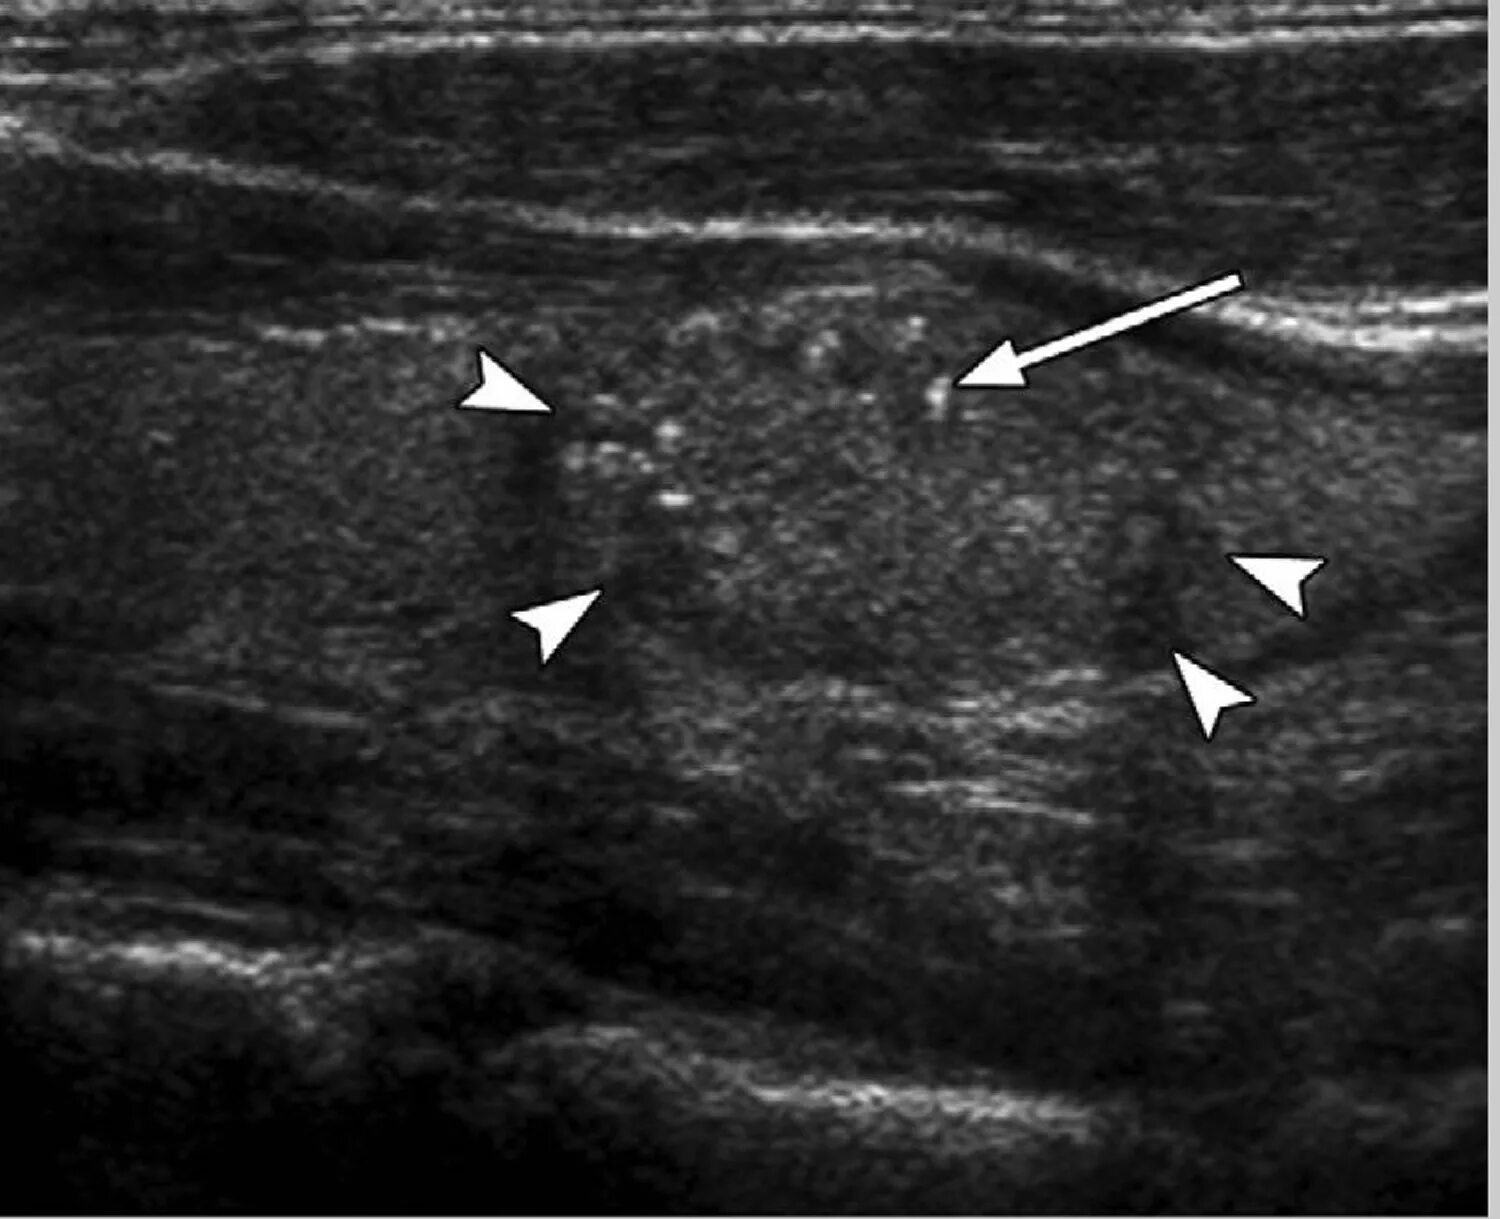

Белое пятно на узи